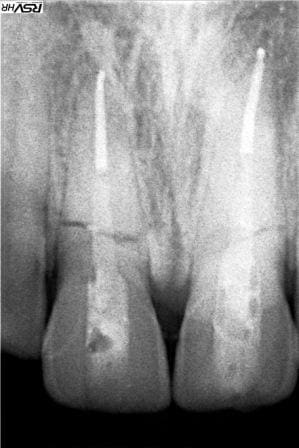

Rx 11 21 02 reduit kwsfll - Eugenol

Rx 11 21 reduit uoydvy - Eugenol

ce n'est peut être pas très visible sur la radio, mais c'est précisément ce qui a été fait:

je n'ai obturé que le 1/4 apical (je ne voulais pas que le ciment fuse dans la fracture lors de la condensation : donc j'ai ajusté la hauteur de cône necessaire que j'ai ensuite condensé à chaud avec des pluggers rouges et jaunes,

j'ai ensuite placé une tenon en fibre de verre (les seuls tenons suffisamment long pour assurer un brochage efficace:

j'ai procédé à la séquence de collage habituelle :

etching / optibond + activateur / compodual pour le scellement du tenon.

j'ai hésité à sceller le tenon au verre ionomère (moins sensible à l'humidité :

rétrospectivement au regard des arguments de ploc cela aurait peut être suffit.